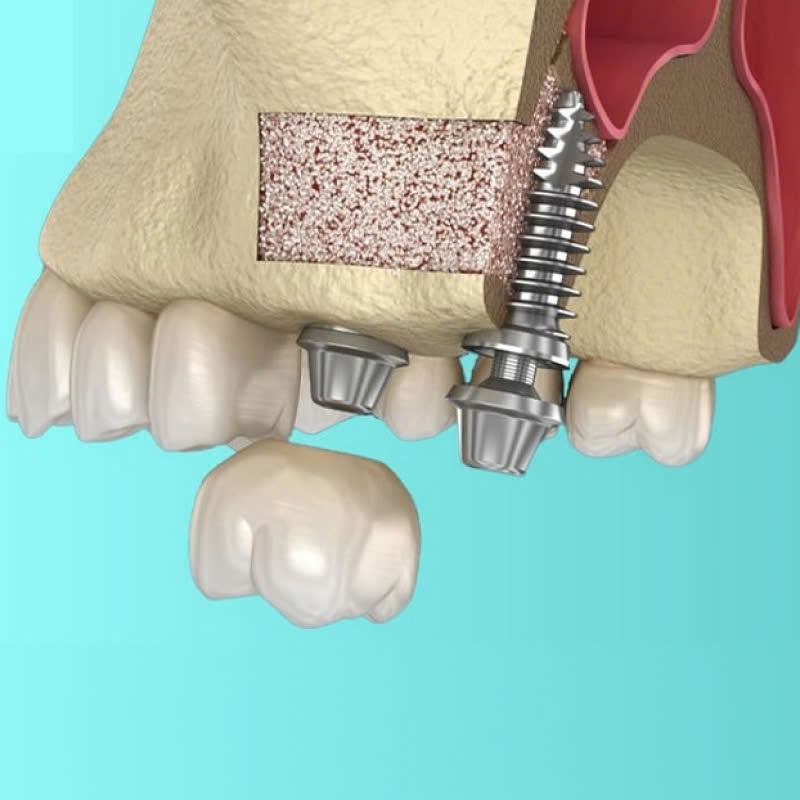

Nâng xoang kín là phương pháp nâng xoang từ bên trong, qua lỗ cấy Implant. Trong quy trình này, bác sĩ sẽ mở một đường rạch nhỏ trên nướu, tạo lỗ để có thể tiếp cận vùng xoang hàm và nâng màng xoang lên. Sau đó, xương hàm cần phải cấy ghép sẽ được đưa vào để có thể lấp đầy khoảng trống.

Bước 5: Ghép xương

Tiếp theo, xương được đưa vào lấp đầy khoảng trống ở vùng xoang hàm.

Bước 6: Cấy implant và khâu vạt nướu

Sau khi ghép xương, bác sĩ sẽ tiến hành cấy trụ Implant và khâu vạt nướu lại.

Thời gian chờ để cấy implant sau khi nâng xoang kín thường dao động từ 4-6 tháng. Đây là thời gian cần thiết cho xương mới hình thành và liền kề với trụ implant một cách vững chắc.